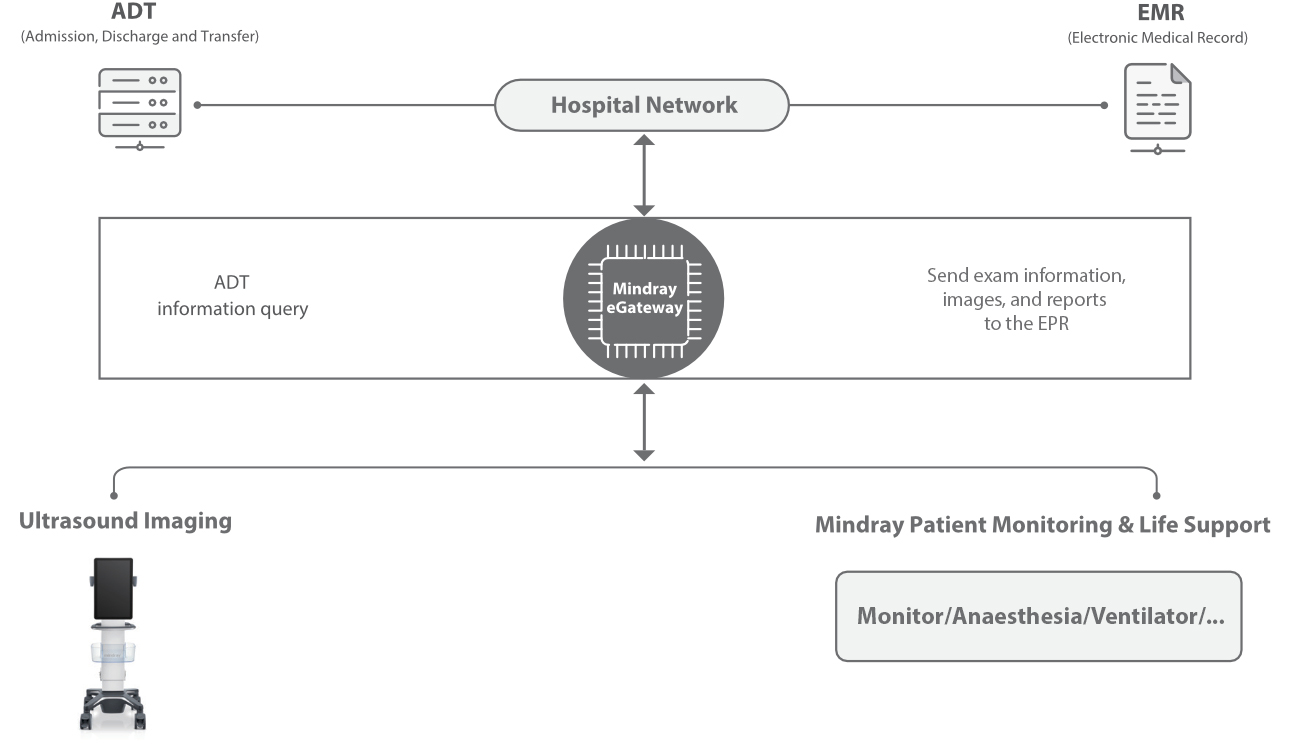

The TE9 Ultrasound System is designed to expand imaging capabilities across point-of-care environments including anaesthesia, emergency, and critical care.

A large clear touchscreen, superior imaging and intelligent diagnostic tools allow the TE9 to support clinical efficiency and diagnostic confidence in high acuity settings. Its compatibility with a wide range of transducers means it can easily adapt to meet point-of-care needs and support a wide range of procedures and diagnostics.

When part of a connected workflow, the TE9 represents a future-proof point-of-care ultrasound solution that can be deployed quickly and reliably ŌĆō supporting clear and reproduceable results.